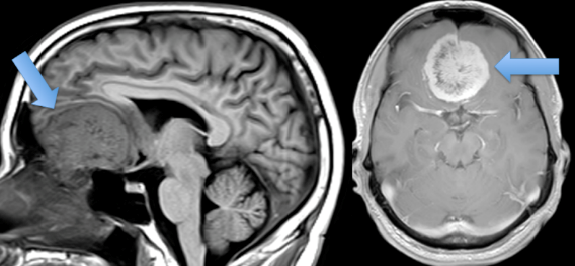

Khối u bất thường gây ra đau đầu (ảnh BSCC).

Bệnh nhân chụp MRI tìm nguyên nhân đau đầu (ảnh BSCC).